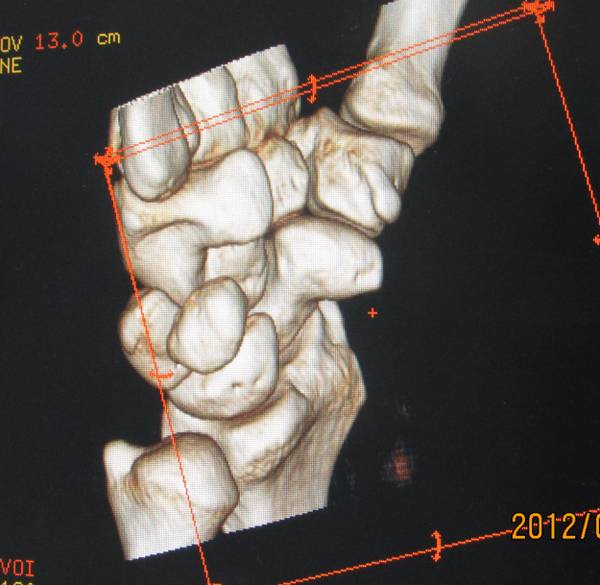

今天去ct室拍了一组舟骨骨图片

在机房看的动态的图像,想怎么看就怎么看

随便转

对骨质结构情况一目了然

太清楚了

舟骨骨折

一侧皮质断裂

平片不明显,幸亏做了CT